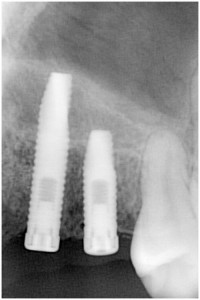

埋入後拡大像

事故により左上34脱落→インプラント埋入

同拡大像